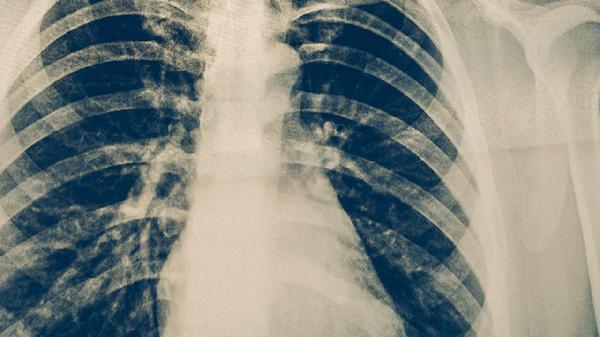

胸部增强CT能清晰显示肺部病灶的血供情况及周围淋巴结转移,对中央型和周围型肺癌均有较高检出率。该检查无创且扫描速度快,可评估肿瘤与血管的关系,为手术可行性提供依据。需注意造影剂过敏者慎用,检查前需空腹4小时。